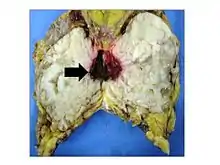

Phyllodes tumors are a fibroepithelial tumor composed of an epithelial and a cellular stromal component. They may be considered benign, borderline, or malignant depending on histologic features including stromal cellularity, infiltration at the tumor's edge, and mitotic activity.[1] All forms of phyllodes tumors are regarded as having malignant potential. A large series from the M.D. Anderson Cancer Centre reported the incidence of each as benign (58%), borderline (12%), and malignant (30%). Malignant phyllodes tumours behave like sarcomas and can develop blood-borne metastases. Approximately 10% of patients with phyllodes tumours develop distant metastases and this can go up to 20% in patients with histologically malignant tumours.[2] The commonest sites for distant metastases are the lung, bone, and abdominal viscera. Rare sites of metastasis, such as to the parotid region, have also been described.[3]

Treatment

The common treatment for phyllodes is wide local excision.[1] Other than surgery, there is no cure for phyllodes, as chemotherapy and radiation therapy are not effective. The risk of developing local recurrence or metastases is related to the histologic grade, according to the above-named features. Despite wide excision, a very high percentage of surgeries yielded incomplete excision margins that required revision surgery.[4] Radiation treatment after breast-conserving surgery with negative margins may significantly reduce the local recurrence rate for borderline and malignant tumors.[6] The authors of a 2012 study have derived a risk calculator for relapse risk of phyllodes tumors after surgery.[7]